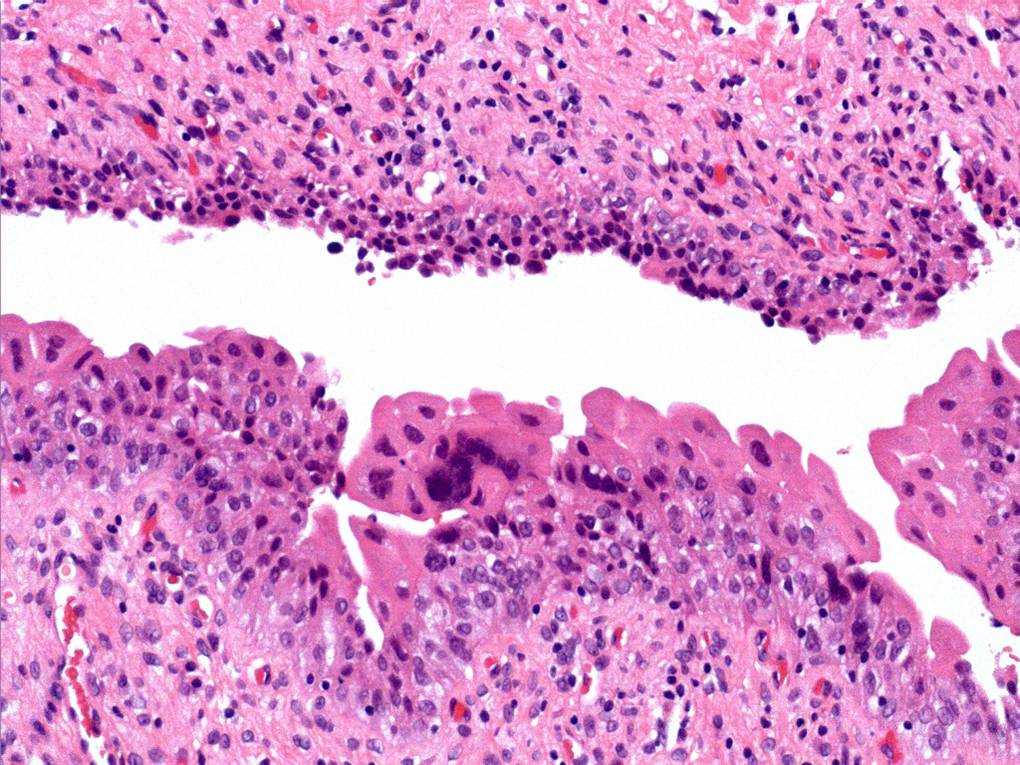

Consensus grade: Reactive atypia

The main change here is ‘degenerative’ nuclear atypia in a rather unusually prominent umbrella cell layer. The underlying urothelium shows mild reactive changes in places with some chronic inflammation in the lamina propria.